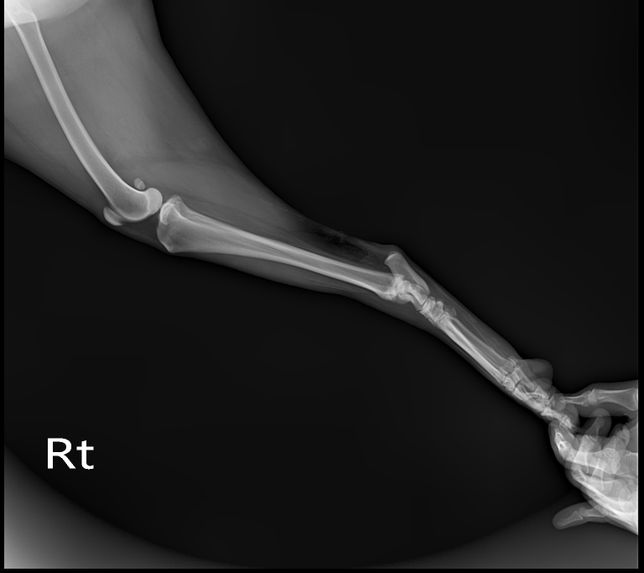

Q. 강아지 엑스레이상 문제 없는데 발이 왜 이상할까요?계단 오르다 발을 헛딛고 못 딛어서 엑스레이찍어 봤는데 엑스레이상 문제는 없다고 하셨어요 하지만 현재 발 모양이 이상해서요 인대 문제라고 하셨는데 인대로 인한 발 모양이 변했다면 언제쯤 다시 돌아 올까요? 삼일째 되는 날 발을 중간중간 딛기는 하는데..너무 걱정되네요 다른 의견도 듣고 싶어 질문 합니다.다친발 사진정상 발 사진

• 강아지 엑스레이상 문제 없는데 발이 왜 이상할까요?의 0번 째 이미지

• 강아지 엑스레이상 문제 없는데 발이 왜 이상할까요?의 1번 째 이미지

• 강아지 엑스레이상 문제 없는데 발이 왜 이상할까요?의 2번 째 이미지

• 강아지 엑스레이상 문제 없는데 발이 왜 이상할까요?의 3번 째 이미지